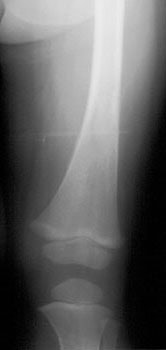

Plain film findings in neuroblastoma include multicentric lytic skeletal lesions, metaphyseal lucent bands, and vertebral body collapse. Calcification is evident in at least 30% of cases [16]. On IVP there is typically inferior renal displacement rather than collecting system distortion (seen in Wilm's)

On CT neuroblastoma typically appears as a large complex mass which is often locally invasive into adjacent tissue and typically encases the great vessels, although a pseudocapsule maybe seen. Neuroblastomas often contain areas of necrosis, hemorrhage, and calcification (seen in between 50% to 80-85%). Calcification is usually coarse, amorphous, and mottled, but can be curvilinear or nodular. The mass may appear cystic and can mimic an adrenal hemorrhage in neonates. Neuroblastomas appear bright on T2-weighted MRI images.